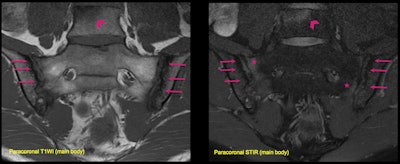

A 36-year-old man presented with lower back pain. Structural lesions are visible in paracoronal T1-weighted imaging (T1WI), including erosions and subchondral sclerosis (arrows). Paracoronal STIR in the same patient shows subchondral edema (asterisks), consistent with active inflammation. Note that the changes are bilateral and symmetrical, but more severe at the iliac sides of the joints. There is also an inflammatory Romanus lesion at the anterior corner of the L5 vertebral body (arrowheads) with an erosion and adjacent bone marrow edema. These findings together suggest ankylosing spondylitis. Remember to look at the main body for inflammatory disorders. All images courtesy of Dr. José Acosta Batlle et al and presented at RSNA 2023.